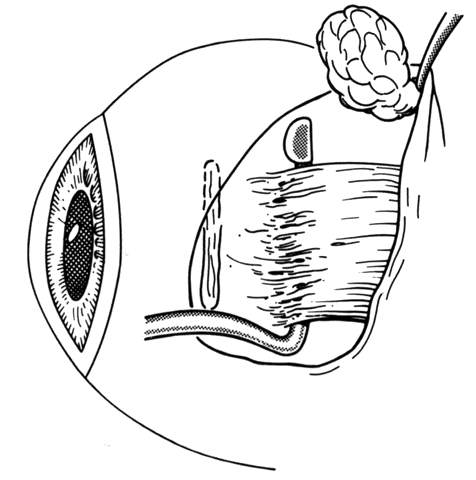

Fig. 3. This diagram demonstrates the findings of surgical exploration of the patient in Figure 2.

Fig. 4. Failure to incorporate a portion or the entire tendon of the muscle when sutures are placed near the insertion can permit a portion or all of the muscle to slip posteriorly and produce an exaggerated recession effect. On exploration, the muscle capsule will be present but the tendon will be retracted within the muscle capsule.